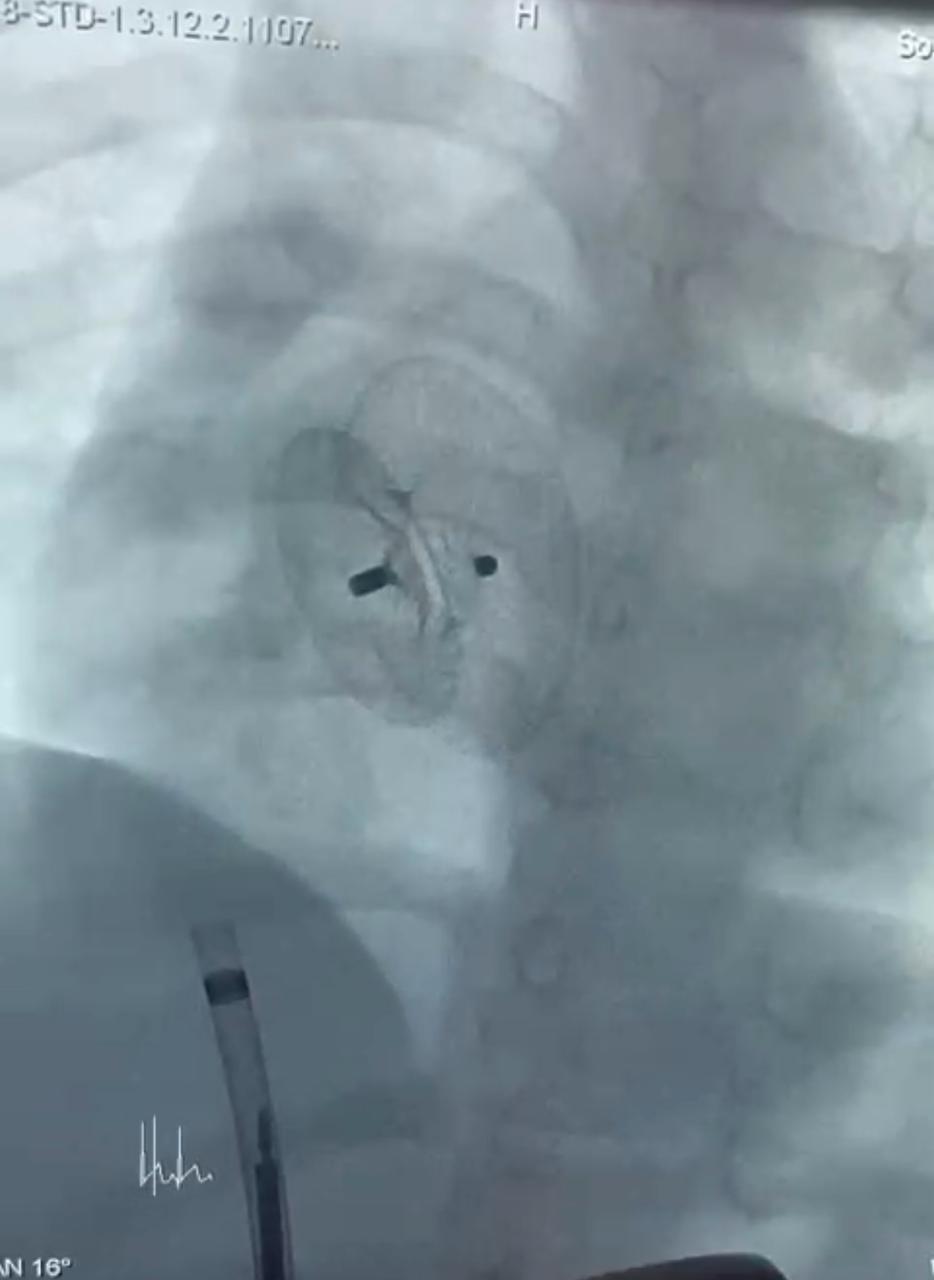

نجح الفريق الطبي بوحدة قسطرة الأطفال جامعة سوهاج، في إجراء ثلاث عمليات دقيقة ومعقدة بالقسطرة التداخلية لأطفال تتراوح أعمارهم بين ٣ و١٣ عامًا، في إنجاز طبي جديد يُضاف إلى سجل مستشفى سوهاج الجامعي، وذلك خلال يوم واحد فقط، باستخدام أحدث الأجهزة والتقنيات.

وقال الدكتور مجدي القاضي، عميد كلية الطب البشري ورئيس مجلس إدارة المستشفيات الجامعية جامعة سوهاج، بأن العمليات الثلاث تمثل نقلة نوعية في علاج العيوب الخلقية بالقلب لدى الأطفال، حيث تمت بإستخدام القسطرة التداخلية دون الحاجة إلى تدخل جراحي مفتوح، مما يُسهم في تقليل المضاعفات وتسريع معدلات الشفاء.

وأوضح الدكتور أحمد كمال عبدالحميد، المدير التنفيذي للمستشفيات الجامعية جامعة سوهاج، أنه تم علاج الطفلة حور (٣ سنوات) والتي كانت تعاني من ثقب بين الأذنين، وتم غلقه بإستخدام جهاز أمبلاتزر، والطفلة مريم علي (٦سنوات) التي كانت تعاني من ثقب بين الأذنين مصحوب بتضخم في القلب ونقص في النمو، وتم علاجها بإستخدام جهاز لايف تك، والطفلة فاطمة (١٣ سنة)، والتي كانت تعاني من ثقب بين البطينين، وتم إغلاقه بإستخدام جهاز كونار لايف تك، وهو من أحدث أجهزة إغلاق الثقوب عالميًا.